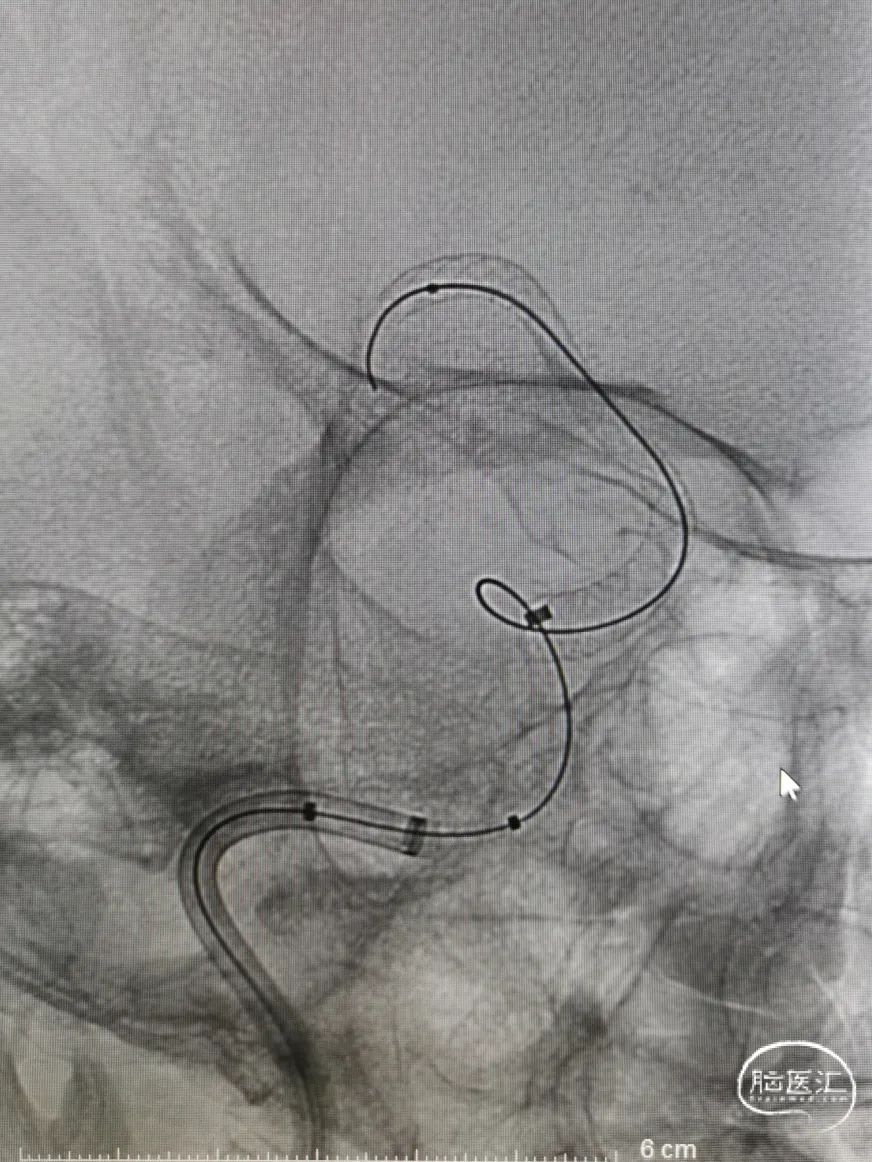

由于颈部血管迂曲明显,选择Neuron MAX 6F 088长鞘顺利到达右颈内动脉C1末端做近端支撑。Synchro 0.014 200微导丝及XT-27微导管引导CAT 5(Catalyst 5)导管同轴越过右颈内动脉末端动脉瘤至右大脑中动脉瘤M1末端后撤出微导丝微导管,保留CAT 5导管。

选取Surpass Streamline 5mm╳40mm经CAT 5导管释放。由于血管迂曲,支架与CAT 5导管摩擦较大,Surpass Streamline无法推出。

图5

将Neuron MAX 6F 088长鞘尽可能送达右颈内动脉岩骨段,将Surpass Streamline在体外推送至支架导管头端MARK点,再经CAT 5导管释放。考虑动脉瘤颈宽大,载瘤动脉瘤样改变,Surpass Streamline远端定位右侧大脑中动脉M1中远段,结合推拉技术,顺利释放Surpass Streamline,并行导丝充分按摩。

图6